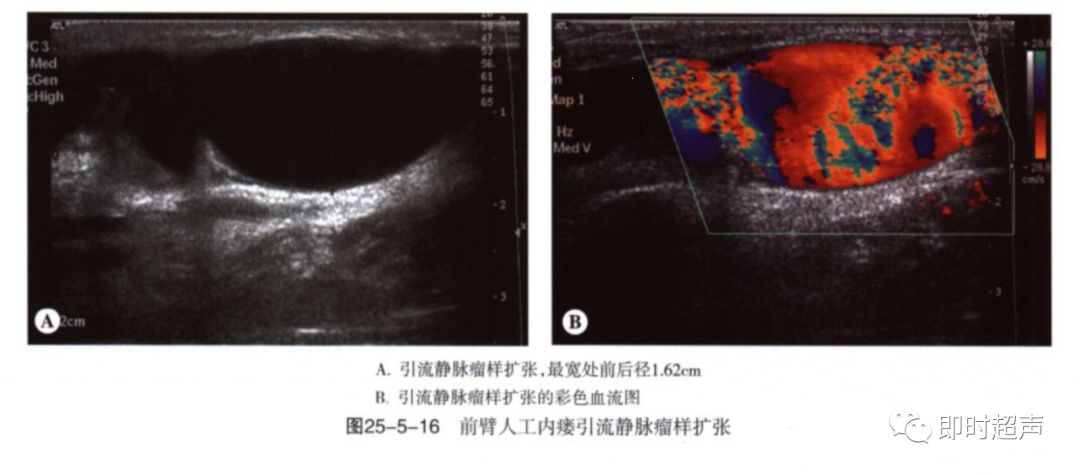

动脉瘤及静脉瘤样扩张